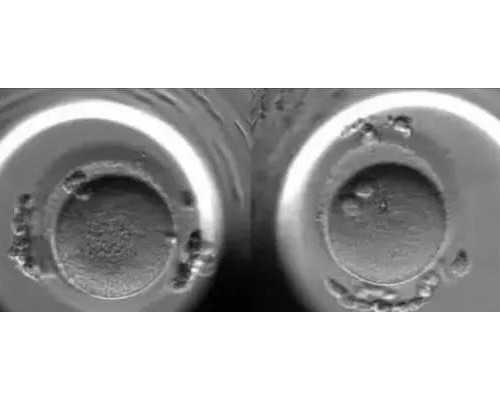

近年来,由于环境污染和精神压力等诸多因素的影响,不孕症发病率呈上升趋势,已成为世界性的医学和社会问题,中国育龄夫妇中不孕症患者占8%-15%。试管婴儿是指从卵巢内取出卵子与精子在体外受精形成胚胎再移植到子宫,着床发育形成胎儿的全过程,在世界范围已经得到迅速发展和广泛应用,是不孕症的重要治疗手段。胚胎移植(ET)是试管婴儿的最后环节,也是最关键的一个步骤。从移植到检查是否怀孕这段时间患者承受的心理压力最大。经常有患者问:“移植后我应注意什么?”尤其是对试管婴儿移植后饮食最为关心。